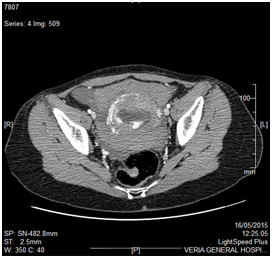

A 31 year old Gravida 3 Para 2 in her 10th+0 week of gestation was brought to our Ob/Gyn department by the ambulance because of acute onset lower abdominal pain followed by a syncopal episode. The patients’ pregnancy was confirmed by an obstetrical ultrasound performed 2 weeks prior to her presentation in our department and was described as a singleton intrauterine pregnancy. Her past obstetrical history included 2 uncomplicated caesarian sections 4 and 1 years earlier. On presentation the patient was hypotensive and tachycardic (BP: 90/60, HR: 102). The patient was resuscitated with IV fluids. On speculum examination a normal vagina and a closed cervix were noted. On bimanual examination the size of the uterus was consistent with a 10 week pregnancy. There was diffuse tenderness on palpation of the abdomen with decreased bowel sounds and Kehr sign positivity. (Acute pain in the tip of the shoulder due to the presence of blood or other irritants in the peritoneal cavity when a person is lying). Her hematocrit and hemoglobin were 23.2% and 7.5g/dL respectively. On transabdominal ultrasound a round gestational sac with a live fetus (CRL 10w+1) were revealed (Figure 1 & Figure 2). The sac was located in the lower anterior uterine segment. Free fluid was noted in the cul-de-sac.

Figure 1 CRL: 10w1d.